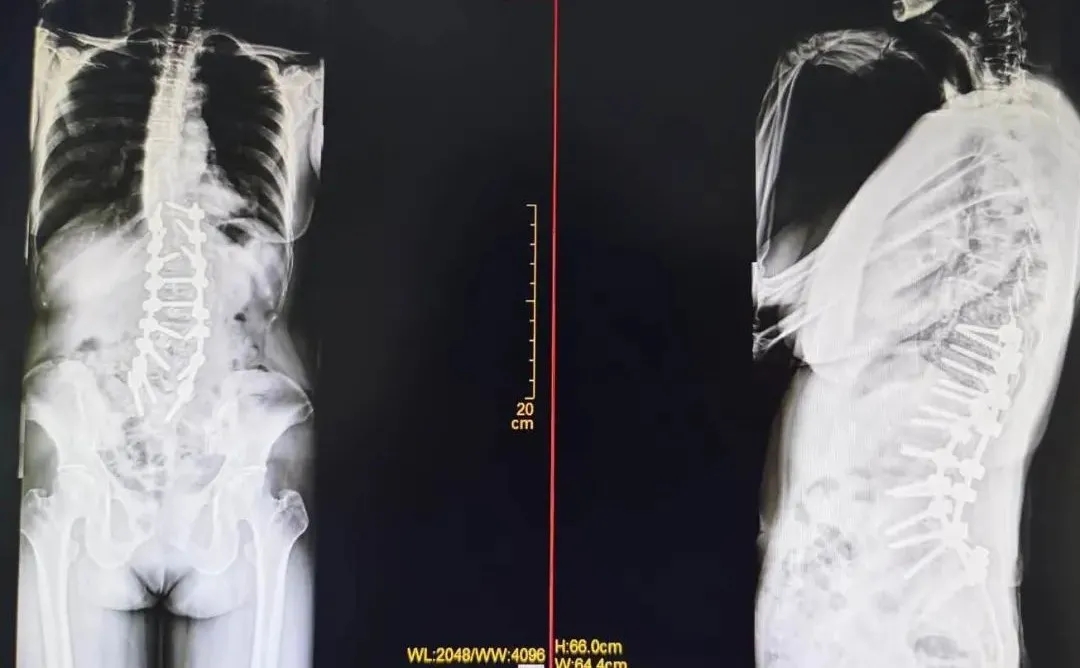

在麻醉科、ICU 和专业神经监护全力配合下,脊柱、骨病外科手术团队为患者顺利地完成了手术,术后患者顺利出院,术后复查随访恢复良好,生活质量得到了很大提高。

“感谢医生让我挺直脊梁,现在我对生活又充满了希望。”患者出院时高兴地说到。

术后三个月复查